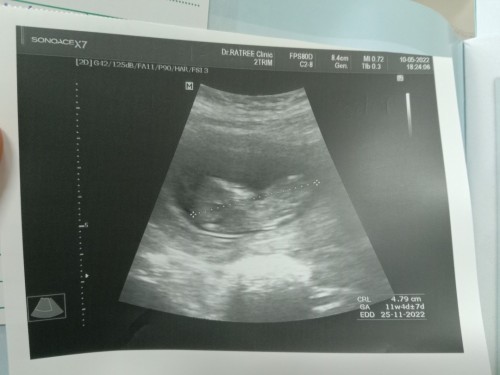

ท้องสอง ซาวด์รอบแรก หนู 11w ท้องสองก็ยังตื่นเต้นเหมือนท้องแรกคะ แม่ๆท้องกี่วีคกันบ้างคะ 🤰❤️☺️